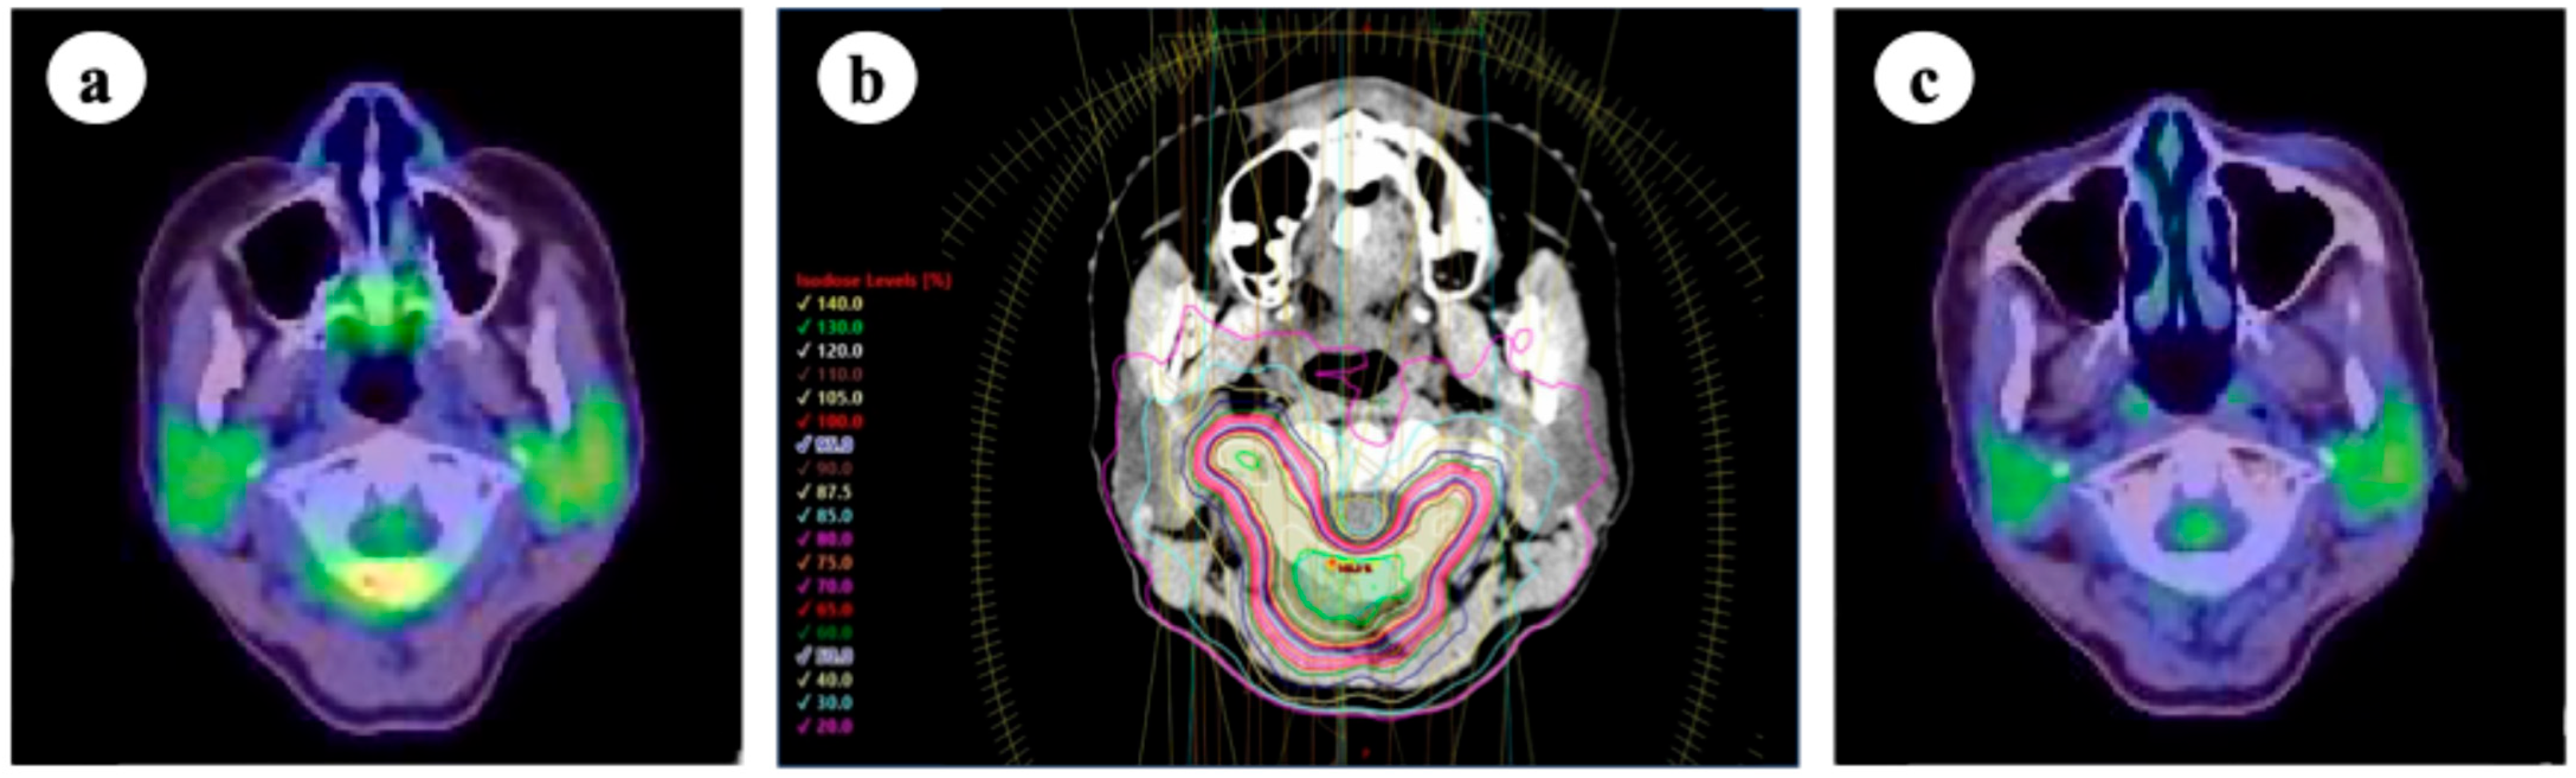

Figure 2.

(a) 18-fluoro-deoxyglucose positron emission tomography/computed tomography (FDG-PET/CT) before stereotactic body radiotherapy (SBRT), showing increased FDG uptake in the left adrenal gland (arrow); (b) SBRT plan for the left adrenal metastasis. SBRT was prescribed with a dose of 40 Gy in five fractions to 95% of the planning target volume (PTV) and 70% isodose lines; (c) FDG-PET/CT scan 1 year after SBRT, demonstrating response in the treated lesion (arrow). No severe adverse events were observed.